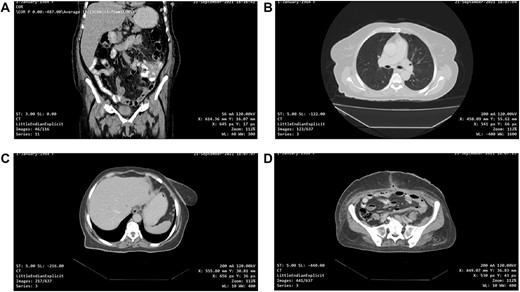

(A and B) CT scan of the abdomen and pelvis demonstrated a large pelvic mass adherent to the sigmoid colon and compressing its surrounding structures.

Abdominal ultrasound revealed a bulky hypoechoic pelvic mass with ill-defined borders. Computed tomography (CT) scan of abdomen and pelvis established a large pelvic mass adherent to the sigmoid colon and compressing its surrounding organs measuring approximately 10 × 11 × 13 cm. (Fig. 1A and B). Initial management included intravenous fluid resuscitation, analgesics and prophylactic antibiotics.

One-month post-operative computed tomography (CT) scan of the chest/abdomen/pelvis revealed: clear lung fields free of metastasis/lymphadenopathy, liver free of metastasis, no retroperitoneal/pelvic lymphadenopathy, no fluid levels near the surgical intervention field, no masses or signs of relapse/recurrence, and kidneys/spleen/genitourinary system are normal (Fig. 6A–D).

(A, B, C and D) One-month post-operative CT scan of the chest/abdomen/pelvis revealing a coronal view of the abdomen and pelvis/lung/liver/surgical site/pelvis free of tumour spread/metastasis/relapse.